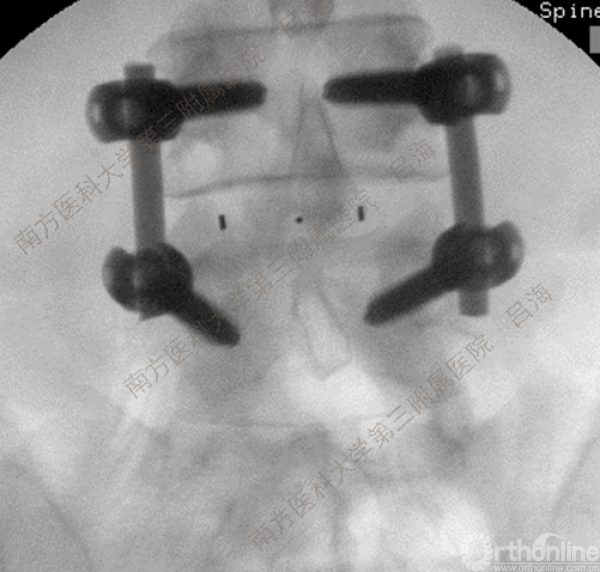

随着社会老龄化进程加快,胸腰椎退行性病变的治疗已经成为脊柱学术界的一个热点话题。MIS-TLIF手术可以治疗多种不同的胸腰椎退行性疾病,南方医科大学第三附属医院吕海教授结合病例为我们一一展示了该术式在治疗不同胸腰椎疾病时的具体手术过程。